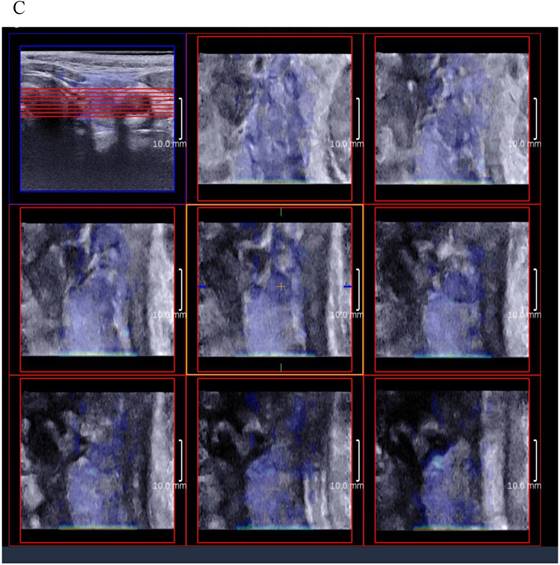

Figure 3

(A) 8 slice images on the sagittal section by 3D SWE of a thyroid papillary carcinoma. (B) 8 slice images on the transverse section by 3D SWE of a thyroid papillary carcinoma. (C) 8 slice images on the coronal section by 3D SWE of a thyroid papillary carcinoma

J Cancer Image J Cancer Image J Cancer Image